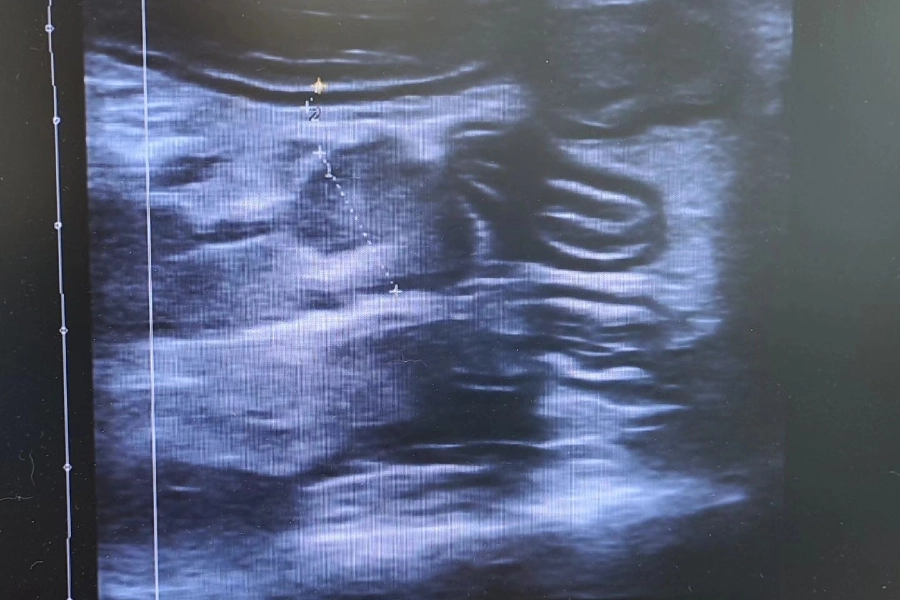

Ο Καμπούρης Ιωάννης είναι Κτηνίατρος και διατηρεί ιδιωτικό κτηνιατρείο στην Καλλιθέα. Είναι απόφοιτος της Κτηνιατρικής Σχολής. Στον χώρο του κτηνιατρείου του, παρέχονται ολοκληρωμένες κτηνιατρικές υπηρεσίες για τους μικρούς φίλους, με έμφαση στη φροντίδα, την πρόληψη και τη θεραπεία. Πραγματοποιούνται χειρουργικές επεμβάσεις, ακτινογραφίες, ενδοσκοπήσεις, καθώς και υπερηχοτομογραφικές αναλύσεις για την ακριβή διάγνωση παθολογικών προβλημάτων. Επιπλέον, παρέχονται εμβολιασμοί, ηλεκτρονική σήμανση (microchip), οδοντιατρικές πράξεις, καθώς και εργαστηριακές εξετάσεις αίματος και ούρων, με στόχο την πλήρη και υπεύθυνη φροντίδα κάθε κατοικιδίου. Το κτηνιατρείο καλύπτει υπεύθυνα κάθε ανάγκη φροντίδας των ζώων συντροφιάς, προσφέροντας υπηρεσίες με συνέπεια, επιστημονική γνώση και σεβασμό απέναντι στους μικρούς ασθενείς.